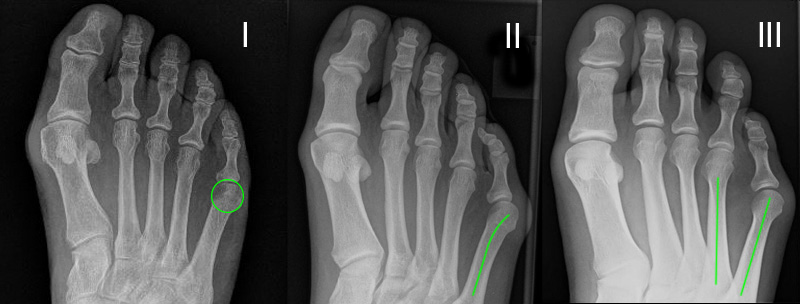

Röntgenmorphologische Einteilung nach Coughlin (I-III) ergänzt durch Fallat (IV) (Arnold 2002) 34

Typ I: Vergrößerter Metatarsale V Kopf

Typ II: Laterale Seitausbiegung des distalen Os metatarsale V

Typ III: Vergrößerter Intermetatarsalwinkel IV/V von mehr als 8°

Typ IV: Kombination von mindestens 2 Typen I-III

Abb. 2: Tailors bunion Typ I bis III (nach Coughlin)